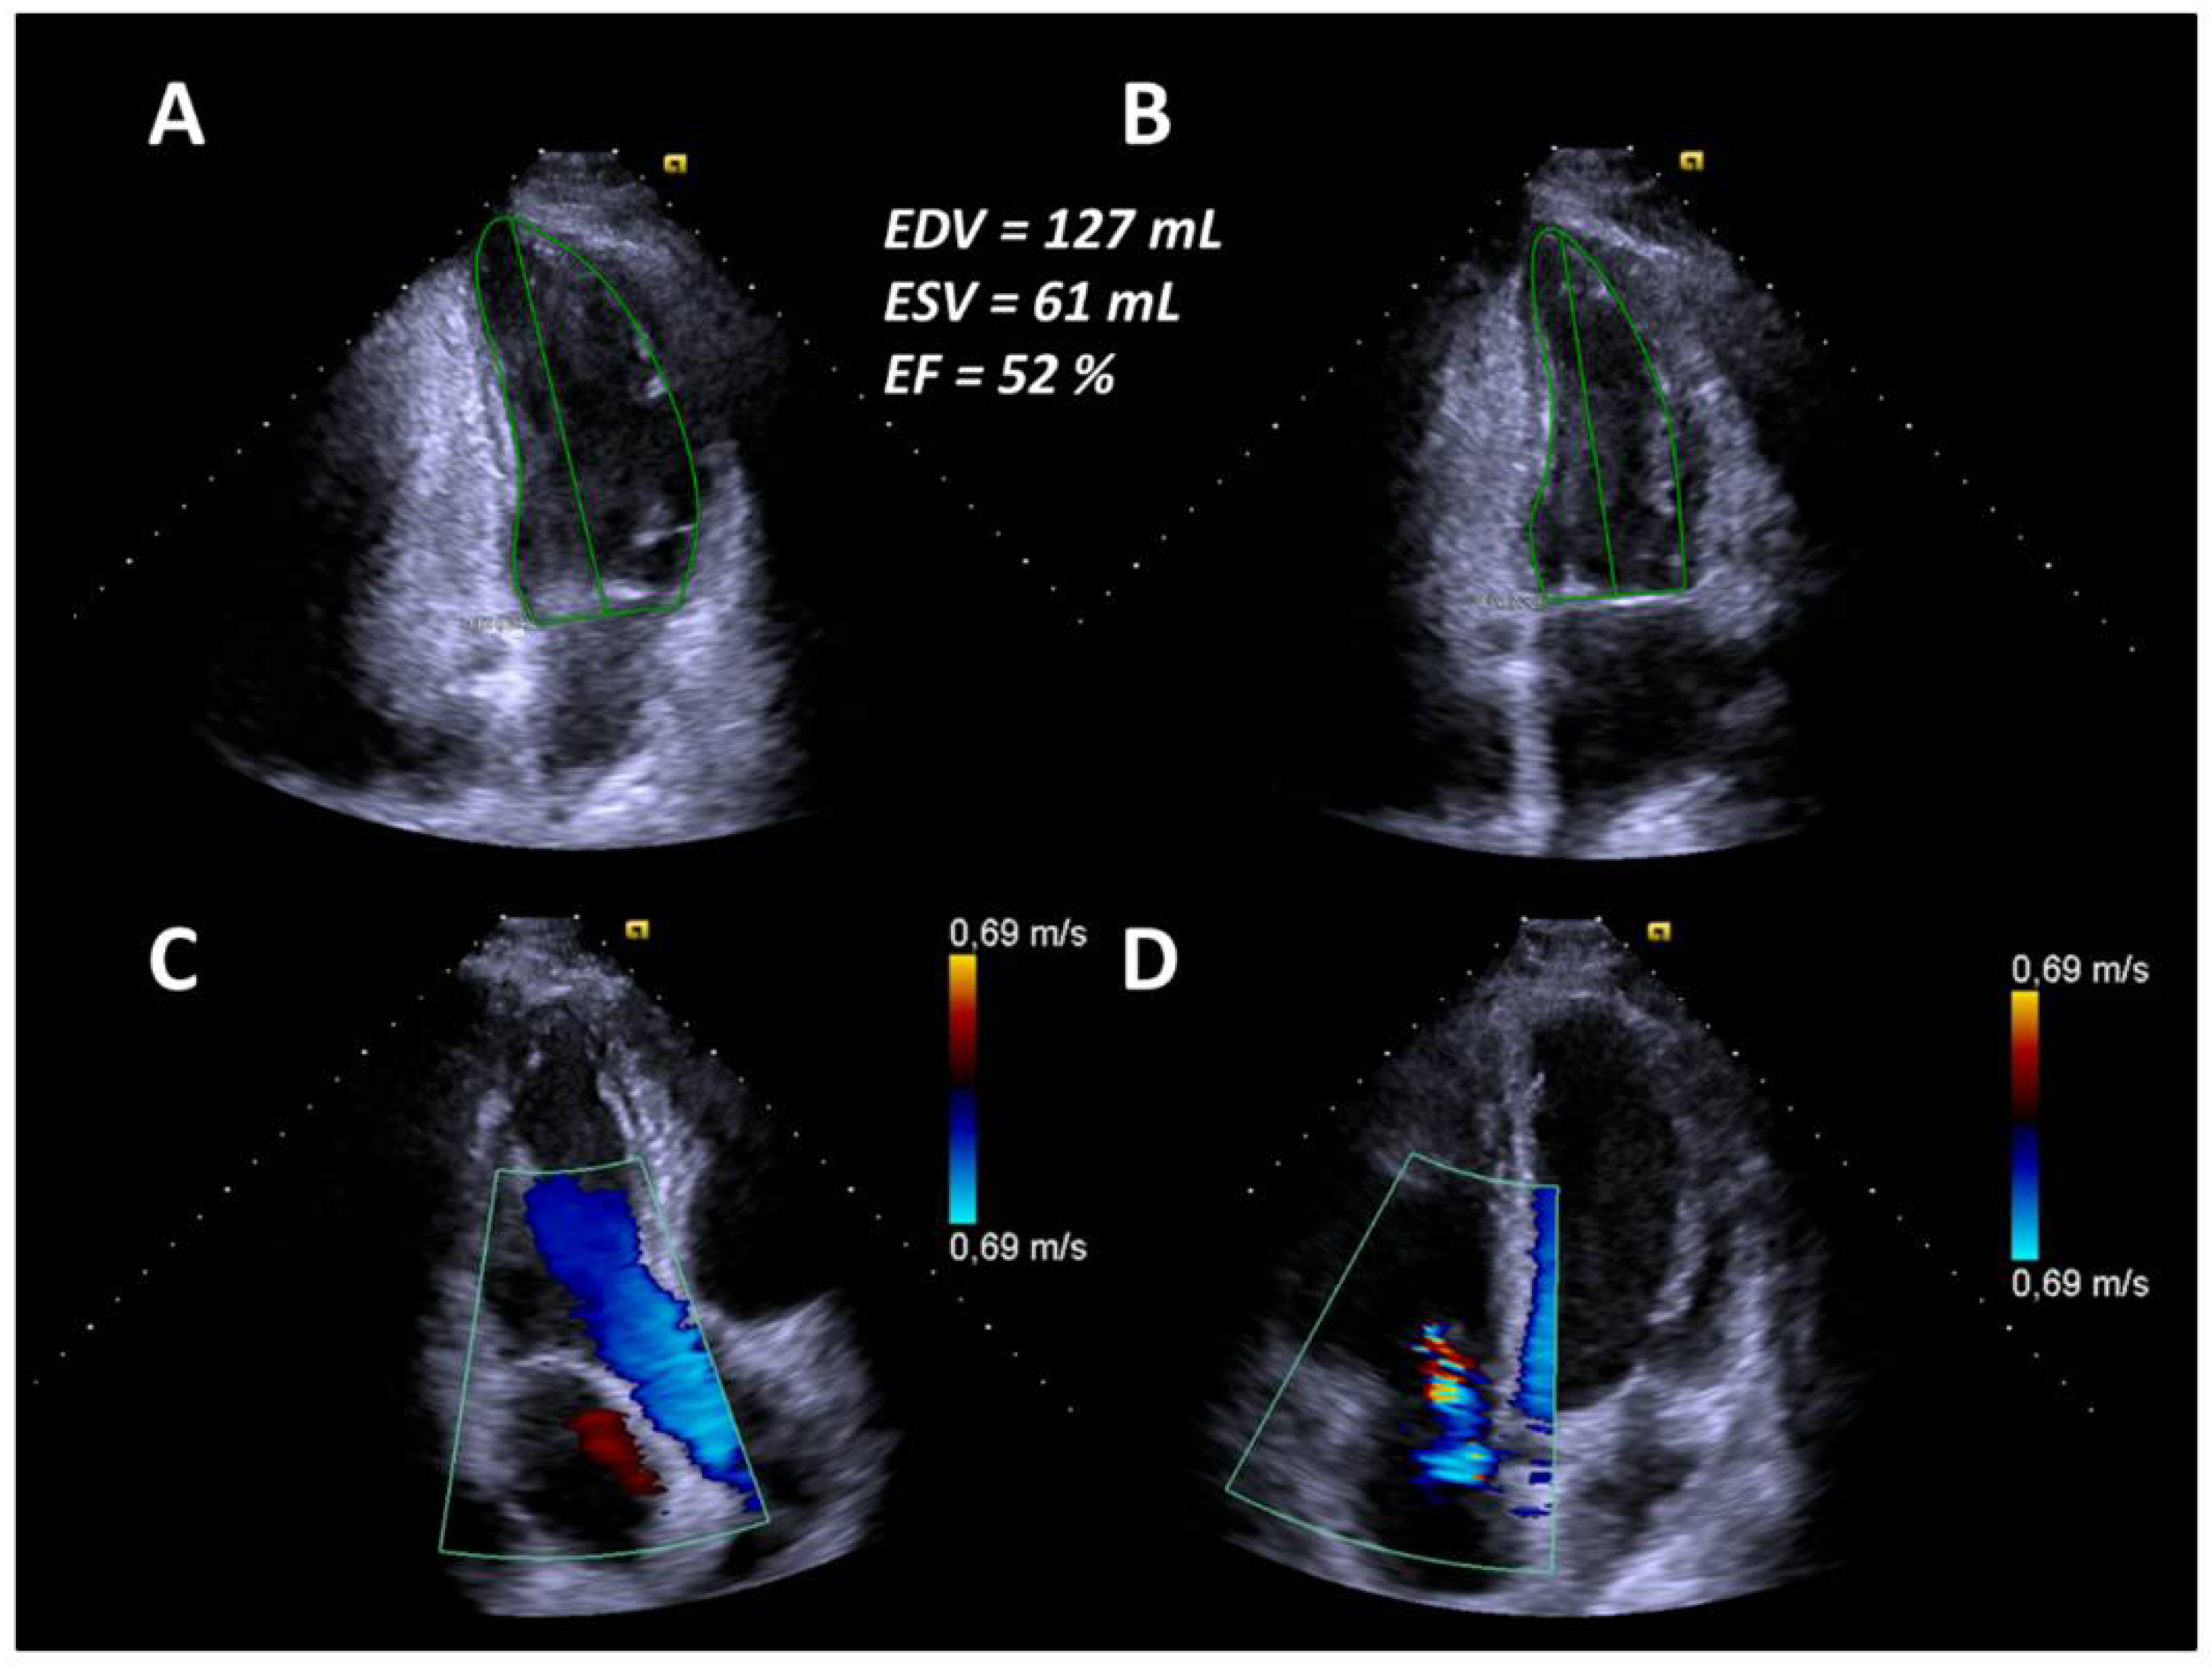

In April 2019, six months after AHSCT, the patient was readmitted due to unusual weakness, fatigue, and newly developed leg edema with a mRSS of 11 points (Figure 1). Laboratory testing revealed elevated NT-proBNP value of 11,189 pg/mL. Echocardiography revealed an LVEF of 32% and pericardial effusion as well as newly developed mitral and tricuspid regurgitation corresponding to acute heart failure (Figure 3).

At the same time, CT changes and spirometric lung function parameters slightly improved. Subsequently, heart failure treatment was intensified with carvedilol, thiazide diuretics, and a higher dose of ACE inhibitors, resulting in concomitant improvement of cardiac parameters. Due to further progression of the disease—despite AHSCT—the patient started on monotherapy with RTX in July 2019. In August 2019, after completion of the first cycle of RTX, clinical symptoms and spirometry parameters ameliorated noticeably (FVC 72.5% predicted, FEV1 79.2% predicted, FEV1/FVC ratio 89.8%), conversely DLCO slightly deteriorated to 38.2% predicted (Figure 1). In October 2019, after completion of the second cycle of rituximab, lung function (FVC 91% predicted, FEV1 95% predicted, FEV1/FVC ratio 84%, DLCO 44% predicted) and mRSS (1 point) further improved significantly (Figure 1). There was also a significant improvement of the echocardiographic findings to a LVEF of 52%, no mitral regurgitation and mild tricuspid regurgitation (Figure 4). Additionally, NT-proBNP levels decreased to 2289 pg/mL.

Figure 3. (A) End-diastolic borders of the left ventricle in the apical two-chamber view. (B) End-systolic borders of the left ventricle in the apical two-chamber view. (C) Mild to moderate mitral regurgitation in the apical three-chamber view. (D) Moderate tricuspid regurgitation in the apical four-chamber view.